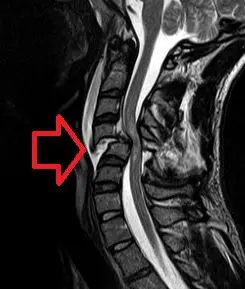

提供的 MRI 影像為頸椎 T2-weighted sagittal view(T2 加權矢狀切面):

- 脊髓壓迫 (Cord Compression):影像中紅色箭頭處(約在 C3-C4 或 C4-C5 節段)顯示明顯的脊髓壓迫。

- 椎間盤突出/骨刺 (Disc Herniation/Osteophyte):壓迫來源看似為椎間盤向後突出或退化性骨刺,導致椎管狹窄 (Spinal stenosis)。

- 脊髓訊號改變 (Cord Signal Change):在壓迫處的脊髓內部出現高訊號影 (High intensity signal),這代表脊髓水腫 (Edema) 或挫傷 (Contusion)。

- 排列 (Alignment):雖然有退化性改變,但並未顯示明顯的椎體滑脫 (Spondylolisthesis,即上位椎體相對於下位椎體明顯向前或向後位移